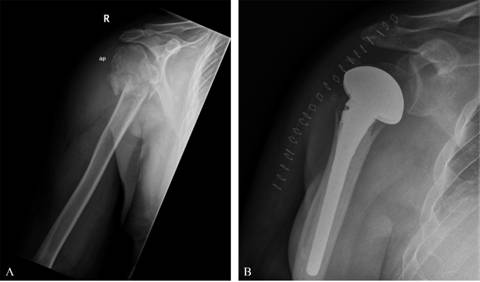

Hombre de 64 años, sin patología de interés previa, al cual se le implantó una hemiartroplastía de hombro derecho (GLOBAL® UNITE® Platform Shoulder System: 12 x 120 mm vástago cementado de 12 x 120 mm y cabeza humeral estándar de 56 mm) por fractura de húmero proximal tras caída desde su propia altura (Figura 1). Tres meses después de la cirugía el paciente acude a urgencias aquejando dolor y malestar en el hombro operado. En el examen físico presentó una tumoración en la cara anterior del hombro con aumento de temperatura local. No tenía otra sintomatología, la movilidad apenas estaba limitada comparada con exploraciones previas y la exploración neurovascular distal era normal. Se decidió realizar estudio radiográfico que no evidenció movilizaciones ni aflojamientos del material protésico. La analítica presentaba alteraciones de los valores relacionados con la inflamación con una VSG de 20 mm/h y una proteína-C reactiva de 2.96 mg/l. Pensando en una posible infección, el paciente fue intervenido y se realizó un lavado artroscópico. Se obtuvieron muestras que se mandaron al departamento de microbiología, sin crecimiento alguno de microorganismos. Fue dado de alta a los dos días de la cirugía con mejoría clínica.

Seis días después de la misma, el paciente presentó un primer episodio de luxación de manera espontánea, sin trauma asociado (Figura 2). Se redujo en quirófano de manera cerrada con sedación y una buena estabilidad. Otro episodio de luxación atraumática ocurrió en los días siguientes. Finalmente tras un tercer episodio en el cual fue necesario recurrir a una reducción abierta, otra vez con buena estabilidad tras la reducción, se decidió realizar una cirugía de revisión, implantando componentes que aportaron mayor estabilidad. (LIMA SMR Total Shoulder Replacement System: 80 x 7 mm vástago tumoral) (Figura 3A).